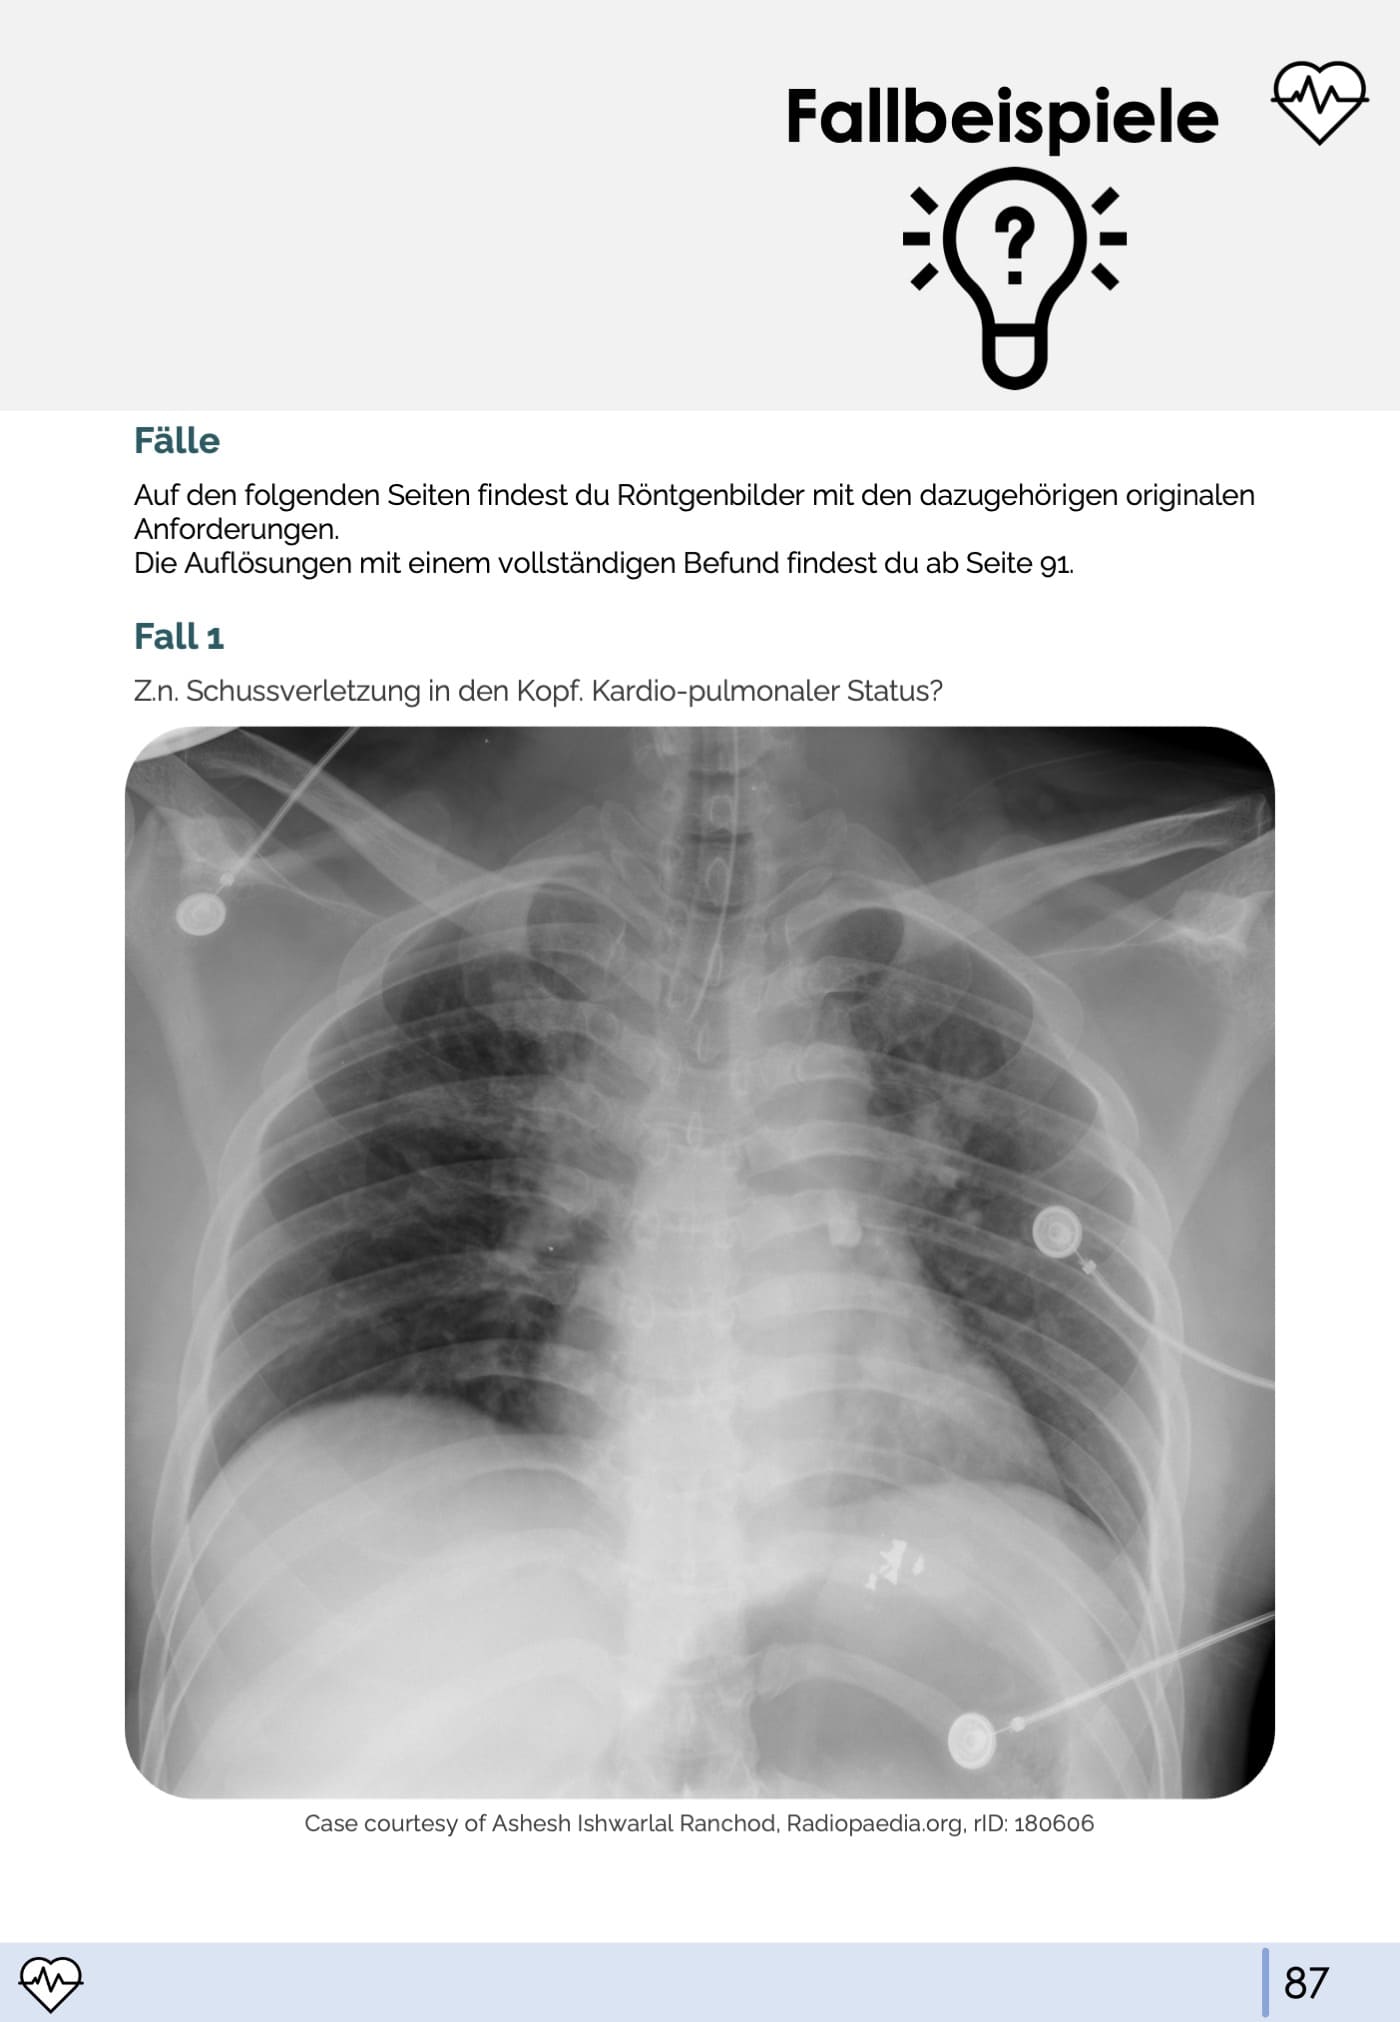

- 9. Fallbeispiele

- Röntgen-Thorax-Befundung üben an echten Fallbeispielen